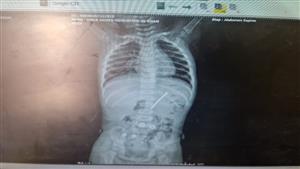

ابتلع المسمار